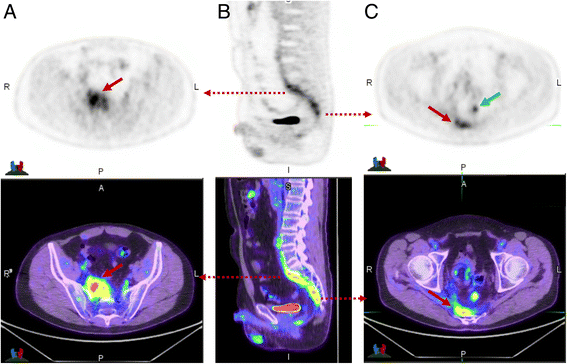

Fig. 5

This patient had suspicion of pelvic recurrence in the setting of prior surgical excision for rectal carcinoma. There was intense uptake in the known pre-sacral soft tissue thickening (a) and (c) (red arrow) with SUVmax of 11. The linear morphology on the coronal image (b) suggested this was more likely inflammatory than malignant. A separate linear tract of metabolic activity was also seen (green arrow) extending from the pre-sacral abnormality to the peri-anal region (not shown). All abnormalities resolved following antiobiotic therapy confirming inflammatory aetiology